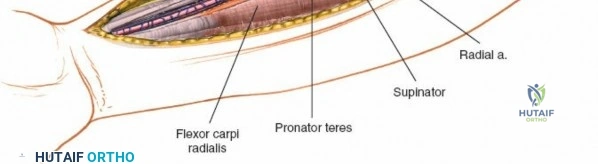

Exposing the proximal third of the radius requires extreme vigilance due to the proximity of the posterior interosseous nerve. The key anatomical landmark here is the insertion of the biceps tendon. Follow the biceps tendon distally to its insertion on the bicipital tuberosity of the radius. A small bursa lies just lateral to the tendon; incise this bursa to gain initial access to the proximal radial shaft. Because the radial artery lies superficial and medial to the tendon at this level, all deep dissection must remain strictly lateral to the biceps tendon.

The proximal radius is draped by the supinator muscle. The PIN passes directly through the belly of the supinator. To protect the nerve, the forearm must be fully supinated. Supination dynamically rotates the radius, carrying the insertion of the supinator anteriorly and simultaneously displacing the PIN laterally and posteriorly, safely away from the surgical field.

With the forearm fully supinated, identify the broad insertion of the supinator on the anterior aspect of the radius. Incise the supinator directly along the line of its insertion onto the bone. It is critical to detach the muscle by dividing its insertion sharply at the bone, rather than splitting the muscle belly, which would risk cutting the PIN.

Proceed with strict subperiosteal dissection, elevating the supinator laterally off the bone. This is one of the rare instances in orthopedic surgery where the safety gained by staying in a subperiosteal plane completely outweighs the theoretical vascular damage to the bone caused by periosteal stripping. The elevated supinator muscle belly now acts as a protective cushion for the PIN.

Retractor Placement and Fixation Technique

Once the proximal radius is exposed, great care must be taken with retractor placement. Never place Hohmann or levering retractors blindly around the posterior surface of the radial neck. Because the PIN may touch the bone posteriorly in up to 25% of patients, a posteriorly placed retractor can easily crush the nerve against the radial cortex. Instead, use gentle right-angle retractors or place retractors only on the anterior and lateral aspects of the bone, utilizing the elevated supinator as a shield.